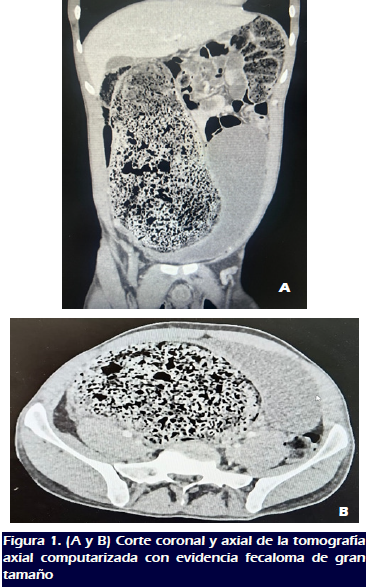

La tomografía computarizada abdominal y pélvica demostró un dolicosigma asociado con un fecaloma gigante, dilatación colónica de 16 cm e hidronefrosis derecha (Figura 1).